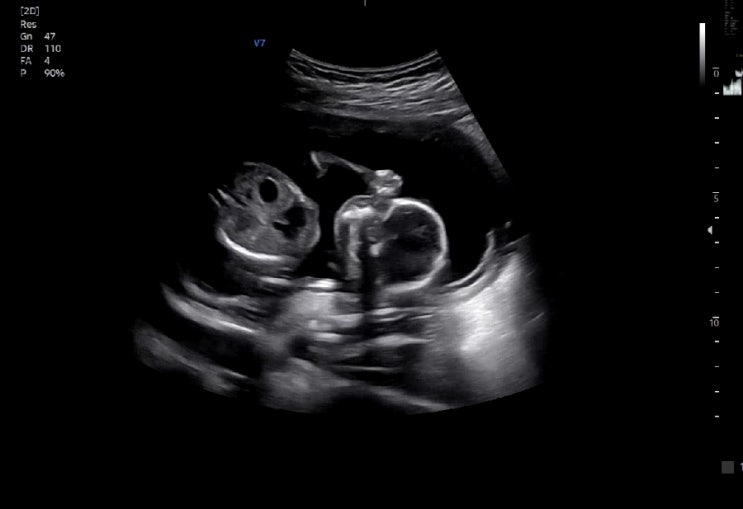

임신 22주차 2차 정밀초음파 / 기형아검사 + 평창 태교여행

임신 16주차 2차 기형아 검사 + 성별 확인

임신 11주 12주 1차 기형아 검사 + 정밀초음파